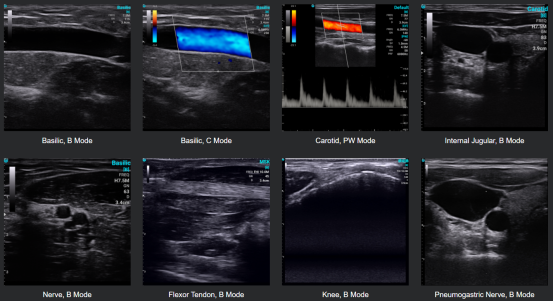

CHISON SonoEye utiliza tecnología de ultrasonido avanzada para producir imágenes de alta calidad. El dispositivo cuenta con un transductor que emite ondas sonoras de alta frecuencia que penetran en el cuerpo y rebotan en el dispositivo, creando imágenes de las estructuras internas. El dispositivo también utiliza algoritmos sofisticados para procesar las imágenes y producir resultados precisos. Para garantizar la precisión durante la medición, SonoEye ha sido equipado con muchas funciones inteligentes, como Auto IMT, PW AutoTrace, software pulmonar profesional, software de guía de agujas, etc. Descubrirá que realizar mediciones precisas puede ser algo muy fácil y rápido.

El ultrasonido portátil SonoEye es versátil para diversas aplicaciones clínicas, incluidas MSK, Cardiología, EMS, Anestesia, obstetra/ginecólogo, Cirugía plástica, y Evaluación vascular, entre otros.